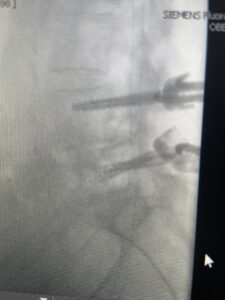

Another patient is a 62 year-old female with progressive low back pain and right leg pain and numbness that radiates to the top of her foot. She tried physical therapy and epidural injections. MRI demonstrated severe L3-4 stenosis and a grade 1 spondylolisthesis (Fig 4). There was L5-S1 and L4-5 disc collapse with modic end-plate changes. Biomechanically because of the significant degeneration of these disc spaces which stiffened the L4-S1 segment more stress was placed on the L3-4 segment, resulting in significant premature degeneration and compensatory stenosis and segmental instability. The MRI also showed pathologically, because of the slip, the L3 inferior processes were more anteriorly oriented and hence contributing to the majority of the lumbar canal compromise. Note the more sagittally-oriented facets in this case compared to the prior case (Fig 5). The patient underwent a decompressive laminectomy with attention of removing the inferior processes of L3 to fully decompress the canal. We also performed an L3-4 fusion with instrumentation (Fig 6). The patient had an uneventful postoperative course with improvement of leg pain. Of note with relief of the disabling leg pain patients are generally very happy. Patients can often manage their low back pain; it is the leg pain that they just can’t tolerate.

Fig 4: Sagittal T2-weighted lumbar MRI demonstrating L3-4 grade 1 spondylolisthesis with severe stenosis (blue arrow)